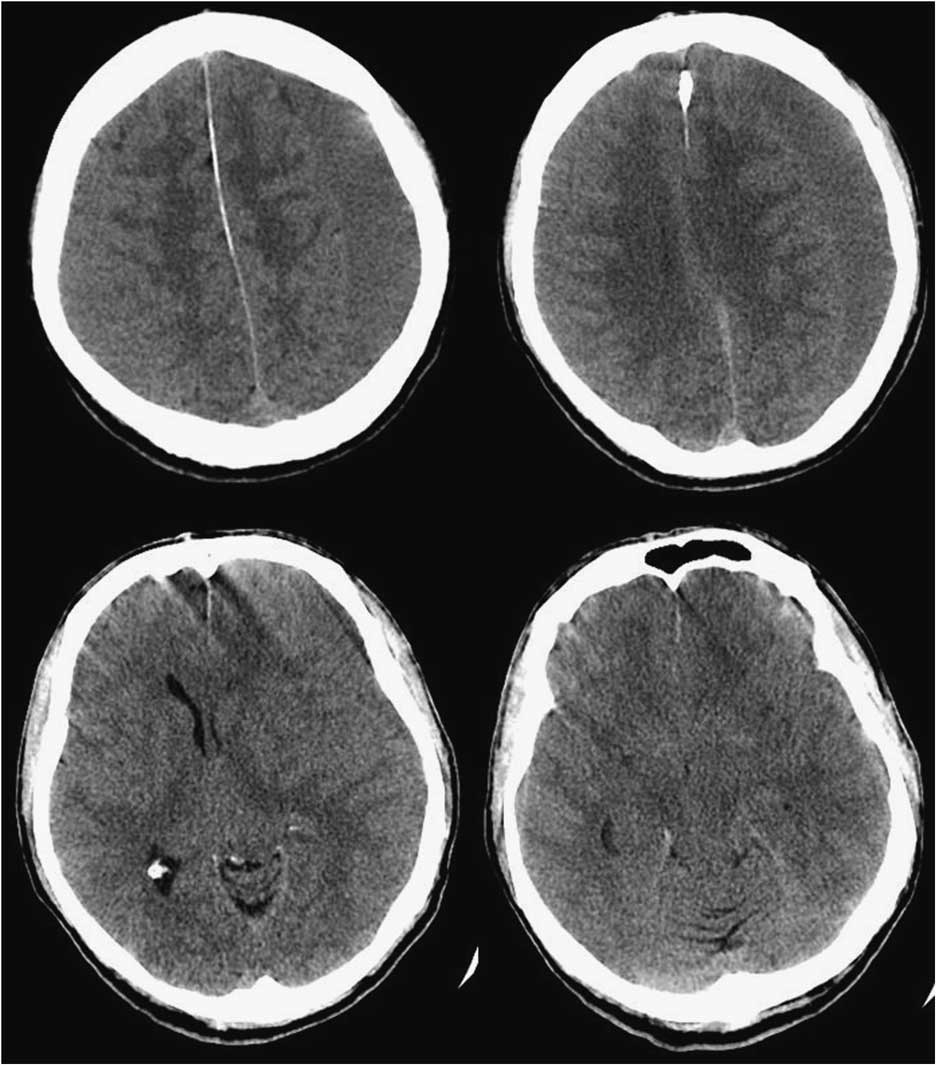

However, repeat CT head suggested worsening SIH with an enlarged left SDH resulting in mild midline shift (Figure 2). A large-volume EBP was performed from spinal levels T2 through S1 to a total volume of 56 ml.Reference Staudt, Pasternak and Sharma 3 After a week, he was free of headache, oriented in all spheres, and had no further hallucinations. However, with the increased left SDH and left-to-right shift, burr hole evacuation was also performed. Upon discharge from the hospital, he remained oriented, with no headache, no psychiatric symptoms, significantly improved cognition (MoCA 29/30) and stable gait. At 3-month follow-up, the patient was headache-free, his chorea was at baseline, he was driving and had resumed work. MoCA was 29/30. MRI showed small bilateral SDHs with improved configuration of the midline brain structures and resolution of brain slumping (Figure 3).

Figure 2 Axial brain CT slices demonstrating enlarged left subdural hygroma with significant left-to-right midline shift.